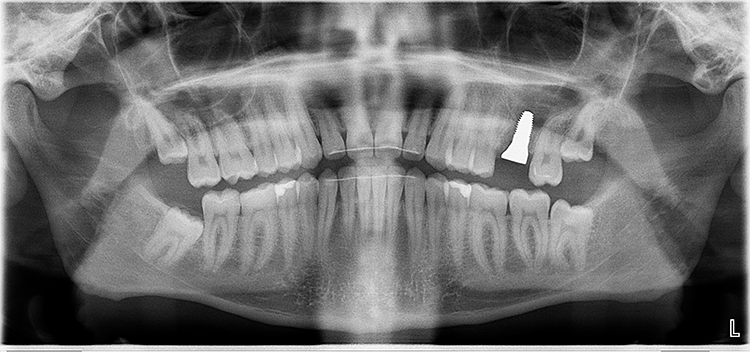

Abb. 2: Repräsentativer Fall von ABH Grad B Septus Typ II. a) Ansichten vor der Installation. Röntgenaufnahme der periapikalen Läsion an einem wurzelkanalbehandelten Molaren und klinische Ansicht der Typ-II-Socket nach der Extraktion. b) Die Ansichten nach der Installation zeigen das Implantat innerhalb des interradikulären Septums und das über dem Implantat platzierte A-PRF. c) Nachuntersuchungen nach 10 Tagen bzw. 2,1 Monaten. Die Röntgenaufnahme zeigt die Knochenbildung zwischen der Sinusmembran und dem apikalen Teil des Implantats. d) Jüngste Nachuntersuchung nach Einsetzen der Prothese.

Abb. 3: Repräsentativer Fall von Grad A Typ I. a) Präoperative Ansicht. Röntgenbild der periapikalen Läsion an einem wurzelkanalbehandelten Molaren. Die Höhe des Alveolarknochens zeigt Grad A an. b) Klinische und radiographische Ansicht der Implantatinsertion unter Verwendung einer Einheilscheibe mit großem Durchmesser (6×8 mm). A-PRF wurde um das Implantat und unter der Scheibe platziert. c) Nachuntersuchung nach 5,9 Monaten vor und nach der Zementierung und Aufbereitung. d) Jüngste Nachuntersuchung nach Einsetzen der Prothese

Bei dem balkonförmigen Implantat blieben die Alveolarkämme und der Kronenansatz erhalten (Abb. 4c und d). Der Spalt zwischen dem Implantat und der bukkalen Lamelle wurde mit A-PRF und einem Kollagenblock aufgefüllt, so dass keine zusätzliche Knochenaugmentation erforderlich war. Zusätzlich wurden PRF-Matrizen um, über, unter und neben dem Implantat im Knochen-Implantat-Raum positioniert (Abb. 1 bis 4b). Außerdem kam eine optionale Einheilscheibe (6 x 8 mm) zum Einsatz, um das Kollagen und die PRF zu sichern (Abb. 3b). Die Implantate zeigten bei einem Drehmoment von 35 Ncm Stabilität, welche mit dem Periotest-Gerät von Medizintechnik Gulden getestet wurde. Die Werte des Implantatstabilitätstests, die im Bereich von –8 bis 0 lagen, wurden als ideal für die Belastung angesehen (Tab. 3).

Querschnittsbilder aus dem DVT zeigen eine hohe Genauigkeit und Zuverlässigkeit bei linearen Knochenmessungen im Zusammenhang mit der Implantatbehandlung [2]. Marginale Knochenniveaus wurden am Schnittpunkt zwischen der Längsachse des Implantats und der mesiodistalen Linie gemessen, die durch den größten krestalen Knochen auf jeder Seite des Implantats markiert ist und als Referenzpunkt für die Messung des Knochenverlusts bei Nachuntersuchungen dient. Trotz der begrenzten Anzahl von Implantaten und der Beschränkungen der Studie wurde eine Überlebensrate von 100% erreicht.